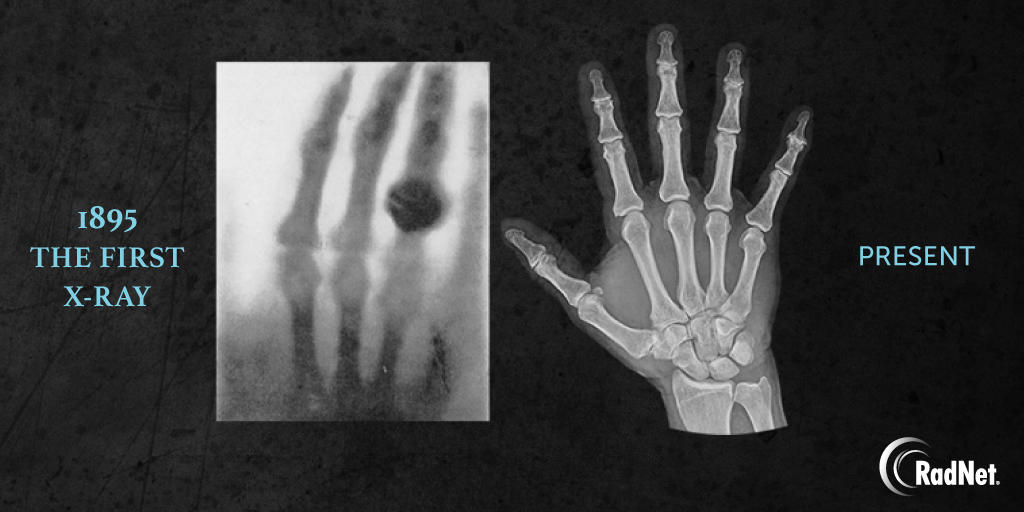

We’ve come a long way since 1895. Happy International Day of Radiology! #RadNet #InternationalDayOfRadiology #Radiology

ProstateMRI's tweet image. We’ve come a long way since 1895. Happy International Day of Radiology!

#RadNet #InternationalDayOfRadiology #Radiology